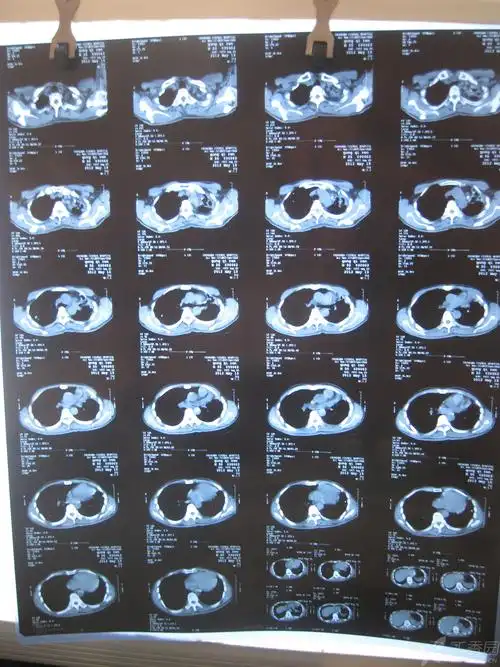

ct诊断肺癌伴有多发转移怎么办?有可能出错吗?还能手术吗?

肺癌的ct诊断